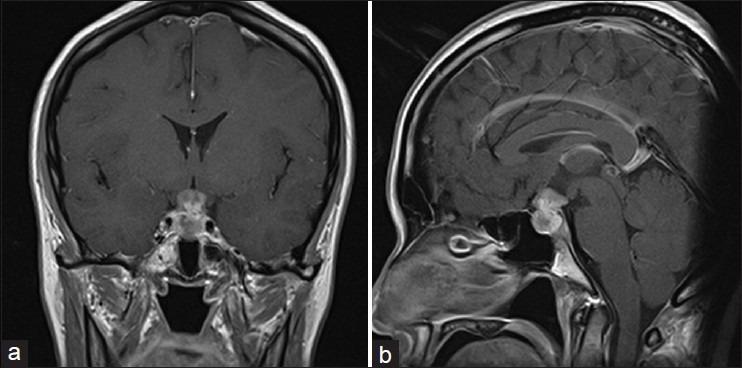

A 44-year-old female complained of visual disturbance. We performed craniotomies twice and removed partially for each time, but any malignant cells were not found in the specimens. Finally, we determined histological diagnosis from the extended lesion. She died of respiratory failure 17 months after the initial treatment.

一名44岁女性主诉视力障碍。我们进行了两次开颅手术,每次均部分切除,但标本中未发现任何恶性细胞。最后,我们从扩大切除的病变中确定了组织学诊断。她在初始治疗17个月后死于呼吸衰竭。